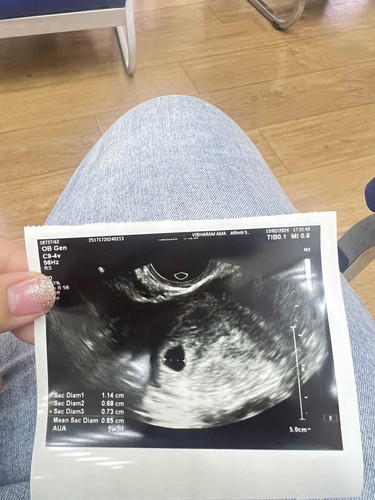

วันนี้มาฝากครรภ์ หมอบอกได้5wแต่ไม่เจอตัวน้อง มีแค่ถุงตั้งครรภ์ แม่ๆท่านอื่นเจอน้องตอนกี่วีคคะ

เป็นเหมือนกันค่ะ ตรวจเจอก็ไปหาหมอไปซาวด์ดู ท้องได้5วีค ไม่เจอตัวเจอแต่ถุง รอไปตรวจอีกทีสิ้นเดือนถ้าไม่เจอตัวอ่อนหมอก็ว่าท้องลม แอบนอยนิด😂

ของเราเจอตอน9วีค3วันค่ะ แต่ไปฝากได้5วีคเหมือนกัน หมอคล้ำหาก็ไม่เจอเหมือนกันค่ะ เลยนัดไปตอน9วีค3วัน เจอน้องและได้ฟังเสียงหัวใจด้วยค่ะ

5วีค5วันยังไม่เจอน้องเหมือนกันค่ะ มีเลือดออกเหมือนประจำเดือน2-3วัน หมอนัดอีกที8วีค แต่ซาวด์ได้8+3เจอน้องแล้วค่ะลุ้นมากกก🥹🥹🥹🥰

ไปฝากครั้งแรก ตอน4วีคเจอแต่ถุงตั้งครรภ์ ไปซาวรอบ2ผ่านช่องคลอดเจอน้องค่ะตอน 6วีค4วัน ปัจจุบัน 9วีค1วันแล้วค่ะ ขอให้เจอน้องนะคะ❤️

บ้านนี้เจอตอน6วีคค่ะ ตอนนี้9วีค5วันค่ะ หัวใจน้องเต้นปกติ แต่ทำงานเดินทั้งวัน ก็แอบลุ้น ซาวอีกรอบ26 ก.พ.นี้ค่ะ

บ้านนี้เจอตอน9วีคค่ะ เห็นดุ๊กดิ๊กแล้วค่ะ ซาวผ่านหน้าท้อง ไปตอน8วีคซาวผ่านหน้าท้องยังไม่เจอเลยค่ะ

ไปซาวตอน5week ไม่เจอเหมือนกันค่ะ วันนี้ไปซาวเจอ 8+6 แล้วจ้า แม่รอก่อนนะคะ ทำใจให้สบายๆ💓🫶🏻

บ้านนี้เจอถุงการตั้งครรภ์และไข่แดงตอน4w4d และเจอตัวน้องตอน10wค่ะ

เจอตอน5+4 เพราะพยายามเพ่งสุดๆและเหมือนเห็นหัวใจน้อยๆกะพริบค่ะ